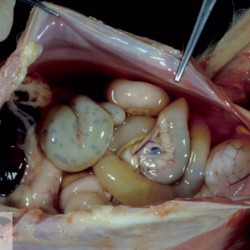

Etiquetes: N-77/99 2 total Canine Specie: Canine Organ: Kidney Lesion: Ascites Lesion modifier: - Disease: Renal insufficiency Files/Expedient: N-77/99 Not viewed Canine Specie: Canine Organ: Oral cavity Lesion: Stomatitis Lesion modifier: Stomatitis - Erosive Disease: Uremic syndrome Files/Expedient: N-77/99 Not viewed Títol Select...Avian (Exotic) (110)Avian (Poultry) (76)Bovine (317)Canine (935)Caprine (47)Equine (257)Feline (326)Ferret (19)General (127)Marine mammal (22)Non-human primate (20)Ovine (328)Porcine (379)Rabbit (61)Reptile (38)Rodent (28)Wildlife (91) Format Select...- (60)Abomasum (37)Adrenal gland (10)Blood (7)Blood vessel (50)Body as a whole (19)Bone (57)Bone marrow (21)Brain (93)Cloaca (1)Diaphragm (2)Ear (5)Esophagus (39)Eye (16)Fetus (12)Gallbladder (23)Gizzard (2)Heart (265)Intestine (356)Joint (32)Kidney (443)Larynx (5)Liver (326)Lung (264)Lymph node (91)Mammary gland (10)Mediastinum (1)Muscle (22)Nasal cavity (22)Nerve (7)Omasum (5)Oral cavity (63)Ovary (14)Oviduct (8)Pancreas (7)Parathyroid (5)Penis (10)Peritoneum (65)Pharynx (9)Pituitary gland (6)Placenta (7)Prostate (8)Proventriculus (3)Reticulum (1)Rumen (28)Sinus (7)Skin (181)Spinal cord (15)Spleen (105)Stomach (125)Teeth (1)Testicle (11)Thoracic cavity (31)Thymus (13)Thyroid gland (5)Tongue (32)Tonsils (11)Trachea (11)Urethra (5)Urinay bladder (61)Uterus (27)Vagina (1)Vulva (1)Yolk sac (1) Cobertura Select...- (152)Abomasitis (26)Abscess (27)Acidosis (1)Adenocarcinoma (20)Adenoma (9)Aerosacculitis (6)Agenesis (1)Agnathia (1)Alopecia (7)Amyloidosis (12)Aneurysm (6)Angiectasis (1)Anthracosis (1)Arteritis (11)Arthritis (15)Arthrogryposis (6)Artifact (4)Ascites (13)Atelectasis (8)Atherosclerosis (5)Atresia (1)Atrial septal defect (2)Atrophy (10)Autolysis (7)Bronchitis (6)Bronchopneumonia (26)Cachexia (2)Carcinoma (103)Cardiomyopathy (19)Cellulitis (2)Chemodectoma (4)Cholangiohepatitis (4)Cholangitis (19)Cholecystitis (4)Cholestasis (5)Chondrodysplasia (2)Chondrosarcoma (2)Chronic passive congestion (13)Chylothorax (2)Cirrhosis (6)Coelomitis (3)Coenurus cerebralis (4)Colitis (40)Congestion (17)Conjunctivitis (5)Coronitis (3)Cryptorchidism (3)Cyst (25)Cystitis (24)Dermatitis (69)Diaphragmatic hernia (4)Dilation (28)Discospondylitis (1)Disseminated intravascular coagulation (7)Dyschondroplasia (1)Dysplasia (29)Ectopia cordis (1)Ectopic ureter (1)Edema (55)Emphysema (5)Encephalitis (5)Endocardiosis (14)Endocarditis (26)Endometritis (5)Enteritis (118)Enterolith (6)Epulis (3)Esophagitis (14)Fasciitis (1)Fibrosis (7)Fibrous osteodystrophy (8)Fistula (1)Folliculitis (3)Fracture (2)Gastritis (34)Gingivitis (5)Glioma (8)Glomerulonephritis (21)Glossitis (25)Glycogenosis (1)Gout (8)Granuloma (2)Granulosa cell tumor (4)Hemangioma (9)Hemangiosarcoma (46)Hematoma (8)Hemoglobinuria (2)Hemopericardium (12)Hemoperitoneum (2)Hemorrhage (100)Hemosiderosis (7)Hemothorax (2)Hepatitis (78)Hernia (11)Histiocytosis (3)Hydatid cyst (11)Hydrocephalus (9)Hydrometra (1)Hydronephrosis (22)Hydropericardium (6)Hydrothorax (3)Hydroureter (5)Hyperkeratosis (8)Hyperostosis (4)Hyperplasia (37)Hypertrophy (9)Hypopigmentation (1)Hypoplasia (7)Hypopyon (1)Impaction (6)Infarction (63)Insulinoma (6)Intussusception (5)Jaundice (17)Laminitis (2)Laryngitis (2)Leiomyoma (5)Leukemia (13)Lipidosis (36)Lipoma (7)Lymphadenitis (45)Lymphadenopathy (7)Lymphangiectasia (6)Lymphangitis (5)Lymphoma (221)Malacia (11)Malignant melanoma (15)Mast cell tumor (11)Mastitis (8)Megaesophagus (2)Melanosis (3)Melena (4)Meningioma (6)Meningitis (6)Meningocele (2)Meningoencephalitis (5)Mesothelioma (5)Methemoglobinemia (2)Mineralization (10)Mucocele (5)Mucometra (1)Multilobular bone tumor (1)Mummification (3)Myelofibrosis (1)Myocarditis (4)Myositis (5)Necrosis (81)Nephritis (113)Nephroblastoma (6)Nephrosclerosis (1)Nephrosis (14)Neuritis (1)Obstruction (13)Omasitis (4)Omphalitis (1)Omphalophlebitis (7)Orchitis (4)Osteoarthrosis (5)Osteomyelitis (9)Otitis (2)Palatoschisis (3)Pancreatitis (3)Panniculitis (3)Papilloma (7)Parakeratosis (14)Patent ductus arteriosus (6)Peliosis hepatis (1)Perforation (17)Pericarditis (35)Peritonitis (39)Persistent right aortic arch (1)Pharyngitis (2)Pheochromocytoma (2)Phlebitis (2)Placentitis (6)Pleuritis (21)Pleuropneumonia (24)Pneumonia (109)Pneumothorax (3)Polycystosis (14)Polyp (5)Polyserositis (6)Posthitis (1)Proctitis (4)Prolapse (3)Prostatitis (3)Proventriculitis (1)Pyelonephritis (24)Pyometra (6)Pyothorax (4)Rhinitis (11)Rumenitis (6)Rupture (24)Salpingitis (3)Sarcoma (57)Sclerosis (1)Scoliosis (2)Seminoma (2)Sequestrum (2)Serous atrophy (14)Sinusitis (7)Splenitis (14)Splenomegaly (9)Spondylitis (6)Spondylosis (1)Stenosis (9)Stomatitis (32)Tenosynovitis (2)Teratoma (3)Thricobezoar (2)Thrombosis (16)Tonsilitis (4)Torsion (13)Tracheitis (4)Tympany (7)Typhlitis (8)Typhlocolitis (4)Ulcer (43)Urethritis (1)Urolithiasis (36)Uroperitoneum (1)Uveitis (1)Vasculitis (15)Ventricular septal defect (3)Volvulus (11) Matèria Select... - (14)- (1653)- (152)Abomasitis - Catarrhal (2)Abomasitis - Catarrhal-hemorrhagic (1)Abomasitis - Chronic (1)Abomasitis - Fibrinous-necrotizing (2)Abomasitis - Hyperplasic (5)Abomasitis - Hyperplasic - Chronic (1)Abomasitis - Necrotic (1)Abomasitis - Necrotizing (2)Abomasitis - Ulcerative (5)Adenocarcinoma (9)Aerosacculitis - Granulomatous (1)Amyloidosis - Chronic (1)Arteritis - Necrotic (2)Arteritis - Necrotizing (1)Arthritis - Chronic (4)Arthritis - Fibrinous-purulent (3)Arthritis - Serous (4)Arthritis - Subacute (1)Ascites - Serous (1)Atrophy - Serous (1)Bronchitis - Catarrhal (3)Bronchitis - Suppurative (1)Bronchopneumonia - Catarrhal-purulent (17)Bronchopneumonia - Fibrinous (1)Bronchopneumonia - Granulomatous (1)Bronchopneumonia - Purulent (1)Bronchopneumonia - Suppurative (5)Carcinoma - Adenocarcinoma (33)Carcinoma - Adenocarcinoma - Hepatocellular (2)Carcinoma - Adenocarcinoma - Mucinous (1)Carcinoma - Basosquamous (1)Carcinoma - Cholangiocellular (3)Carcinoma - Hepatocellular (4)Carcinoma - Metastatic (3)Carcinoma - Squamous cell carcinoma (13)Carcinoma - Transitional cell (2)Cardiomyopathy - Dilated (13)Cardiomyopathy - Hypertrophic (6)Cellulitis - Necrotizing (1)Cholangitis - Chronic (8)Cholangitis - Hyperplasic (3)Cholecystitis - Fibrinous-necrotizing (1)Coelomitis - Fibrinous (1)Coelomitis - Granulomatous (1)Colitis - Catarrhal (3)Colitis - Catarrhal-hemorrhagic (1)Colitis - Fibrinous (1)Colitis - Fibrinous-necrotizing (1)Colitis - Fibrinous-necrotizing (Diphtheritic) (6)Colitis - Granulomatous (2)Colitis - Hemorrhagic (4)Colitis - Hemorrhagic-necrotizing (3)Colitis - Necrotizing (2)Colitis - Ulcerative (6)Congestion - Chronic (2)Conjunctivitis - Hyperplasic (1)Conjunctivitis - Purulent (3)Coronitis - Ulcerative (1)Cystitis - Chronic (3)Cystitis - Fibrinous (1)Cystitis - Fibrinous-necrotizing (1)Cystitis - Follicular (1)Cystitis - Hemorrhagic (6)Cystitis - Hemorrhagic-ulcerative (1)Cystitis - Necrotizing (9)Cystitis - Perforated (1)Dermatitis - Granulomatous (14)Dermatitis - Hyperkeratotic (10)Dermatitis - Hyperplasic (proliferative) (1)Dermatitis - Hyperplastic (10)Dermatitis - Necrotizing (4)Dermatitis - Pustular (4)Dermatitis - Ulcerative (2)Dilation - Chronic (1)Discospondylitis - Necrotizing (1)Dysplasia - Follicular (5)Edema - Interstitial (6)Emphysema - Interstitial (1)Encephalitis - Granulomatous (1)Encephalitis - Nonsuppurative (1)Endocardiosis - Mitral (7)Endocardiosis - Mitral - Chronic (5)Endocarditis - Valvular (6)Endocarditis - Valvular - Mitral (7)Endocarditis - Valvular - Pulmonic (1)Endocarditis - Valvular - Subacute (1)Endocarditis - Valvular - Subaortic (5)Endocarditis - Valvular - Tricuspid (4)Endometritis - Purulent (3)Endometritis - Purulent-hemorrhagic (2)Enteritis - Catarrhal (23)Enteritis - Catarrhal - Acute (1)Enteritis - Catarrhal-hemorrhagic (5)Enteritis - Catarrhal-hemorrhagic - Acute (2)Enteritis - Fibrinous (16)Enteritis - Fibrinous - Acute (3)Enteritis - Fibrinous-necrotizing (7)Enteritis - Granulomatous (14)Enteritis - Granulomatous - Chronic (1)Enteritis - Granulomatous - Multifocal (1)Enteritis - Hemorrhagic (17)Enteritis - Hemorrhagic - Acute (1)Enteritis - Hemorrhagic-necrotizing (1)Enteritis - Hyperplasic (proliferative) (4)Enteritis - Necrotizing (4)Enteritis - Necrotizing - Acute (1)Enteritis - Necrotizing - Hemorrhagic (1)Enteritis - Necrotizing-ulcerative (2)Enteritis - Ulcerative (1)Enteritis - Ulcerative-hemorrhagic (1)Esophagitis - Erosive-ulcerative (6)Esophagitis - Necrotizing (4)Esophagitis - Ulcerative (1)Esophagitis - Ulcerative-necrotizing (1)Fasciitis - Fibrinous-purulent (1)Folliculitis - Purulent (2)Gastritis - Catarrhal (2)Gastritis - Chronic (1)Gastritis - Follicular (1)Gastritis - Hemorrhagic (2)Gastritis - Hemorrhagic-necrotizing (1)Gastritis - Hypertrophic (2)Gastritis - Inclusion bodies (1)Gastritis - Mineralization (1)Gastritis - Mycotic (1)Gastritis - Necrotizing (2)Gastritis - Ulcerative (6)Gastritis - Uremic (3)Gingivitis - Erosive (2)Gingivitis - Hyperplasic (proliferative) (1)Gingivitis - Necrotizing (1)Glomerulonephritis - Chronic (7)Glomerulonephritis - Membranoproliferative (3)Glomerulonephritis - Membranoproliferative - Chronic (1)Glomerulonephritis - Membranous (3)Glomerulonephritis - Membranous - Chronic (1)Glomerulonephritis - Proliferative (2)Glomerulonephritis - Subacute (1)Glossitis - Erosive (2)Glossitis - Granulomatous (6)Glossitis - Hyperplasic (1)Glossitis - Hyperplasic (proliferative) (2)Glossitis - Hyperplastic (1)Glossitis - Necrotizing (2)Glossitis - Necrotizing - Focal (1)Glossitis - Ulcerative (6)Glossitis - Ulcerative - Multifocal (1)Glossitis - Ulcerative - Subacute (1)Glycogenosis (1)Granuloma - Eosinophilic (1)Hemangiosarcoma - Metastatic (2)Hemorrhage - Acute (1)Hemorrhage - Subcapsular (3)Hepatitis - Abscess (9)Hepatitis - Acute (3)Hepatitis - Chronic (4)Hepatitis - Chronic interstitial (6)Hepatitis - Granulomatous (7)Hepatitis - Interstitial - Multifocal (1)Hepatitis - Interstitial - Subacute (1)Hepatitis - Necrotizing (17)Hepatitis - Necrotizing - Acute (2)Hepatitis - Necrotizing - Hemorrhagic (1)Hepatitis - Necrotizing - Subacute (1)Hepatitis - Pyogranulomatous (7)Hepatitis - Subacute (4)Hydronephrosis - Chronic (1)Hydropericardium - Chronic (1)Hyperplasia - Erythroid (1)Hyperplasia - Lymphoid (3)Hyperplasia - Myeloid (1)Hyperplasia - Nodular (8)Hypertrophy - Concentric (2)Hypertrophy - Eccentric (3)Infarction - Acute (17)Infarction - Acute - Multifocal (2)Infarction - Chronic (5)Infarction - Chronic - Multifocal (1)Infarction - Subacute (18)Infarction - Subacute - Focal (2)Laminitis - Chronic (2)Laryngitis - Necrotic (1)Laryngitis - Necrotizing (1)Leukemia - Lymphoid leukemia (2)Leukemia - Non-lymphoid leukemia (6)Lipidosis - Multifocal (1)Lipidosis - Panlobular (1)Lipidosis - Panlobular - Generalized (2)Lymphadenitis - Granulomatous (24)Lymphadenitis - Granulomatous - Chronic (3)Lymphadenitis - Hemorrhagic (1)Lymphadenitis - Necrotizing (5)Lymphadenitis - Necrotizing (caseous) (11)Lymphangitis - Granulomatous (1)Lymphangitis - Purulent (1)Lymphangitis - Ulcerative (1)Lymphoma - Alimentary lymphoma (7)Lymphoma - Cutaneous lymphoma (6)Lymphoma - Lymphosarcoma (2)Lymphoma - Mediastinal lymphoma (1)Lymphoma - Multicentric lymphoma (29)Malignant melanoma - Malignant (1)Malignant melanoma - Metastatic (1)Mast cell tumor - Metastatic (1)Mastitis - Fibrinous-purulent (2)Mastitis - Necrotic (1)Mastitis - Purulent (3)Mastitis - Suppurative (1)Meningitis - Fibrinous-purulent (2)Meningitis - Purulent (4)Meningoencephalitis - Necrotizing (3)Meningoencephalitis - Nonsuppurative (2)Mineralization - Metastatic (4)Myocarditis - Fibrous - Chronic (1)Myocarditis - Granulomatous (1)Myositis - Purulent (2)Necrosis - Acute (1)Necrosis - Cortical (5)Necrosis - Follicular (1)Necrosis - Papillary (8)Necrosis - Papillary - Acute (3)Necrosis - Subacute (3)Necrosis - Tubular (6)Nephritis - Embolic (2)Nephritis - Embolic suppurative (7)Nephritis - Granulomatous (27)Nephritis - Granulomatous - Chronic (1)Nephritis - Granulomatous - Multifocal (1)Nephritis - Interstitial (6)Nephritis - Interstitial - Acute (4)Nephritis - Interstitial - Chronic (41)Nephritis - Interstitial - Subacute (12)Nephritis - Purulent (7)Nephritis - Purulent - Acute (2)Nephritis - Purulent - Multifocal (3)Nephrosis - Cholemic (3)Nephrosis - Hemoglobinuric (10)Omasitis - Fibrinous-necrotizing (1)Omasitis - Hyperkeratotic (1)Omasitis - Necrotizing (2)Omphalophlebitis - Fibrinous-purulent (2)Omphalophlebitis - Purulent (3)Orchitis - Necrotizing (1)Osteomyelitis - Necrotizing (7)Osteomyelitis - Purulent (2)Otitis - Necrotizing (1)Otitis - Proliferative (1)Pancreatitis - Acute (1)Pancreatitis - Chronic (1)Pancreatitis - Granulomatous (1)Panniculitis - Fibrinous-purulent (1)Panniculitis - Necrotic (1)Panniculitis - Parasitic (1)Perforation - Acute (2)Pericarditis - Fibrinous (19)Pericarditis - Fibrinous - Subacute (1)Pericarditis - Fibrinous-necrotizing (1)Pericarditis - Fibrinous-purulent (3)Pericarditis - Fibrous (1)Pericarditis - Fibrous - Chronic (1)Pericarditis - Gangrenous (6)Pericarditis - Granulomatous (1)Pericarditis - Granulomatous - Chronic (2)Peritonitis - Acute (1)Peritonitis - Fibrinous (11)Peritonitis - Fibrinous - Subacute (1)Peritonitis - Fibrinous-purulent (5)Peritonitis - Fibrous (3)Peritonitis - Granulomatous (6)Peritonitis - Purulent (1)Peritonitis - Purulent-hemorrhagic (1)Peritonitis - Pyogranulomatous (3)Pharyngitis - Fibrinous-necrotizing (1)Pharyngitis - Ulcerative (1)Pheochromocytoma - Metastatic (1)Phlebitis - Purulent (1)Placentitis - Fibrinous-necrotizing (1)Placentitis - Necrotic (1)Placentitis - Necrotizing (1)Pleuritis - Chronic (1)Pleuritis - Fibrinous (3)Pleuritis - Fibrinous-purulent (2)Pleuritis - Fibrous (2)Pleuritis - Granulomatous (3)Pleuritis - Hyperplastic (2)Pleuritis - Purulent (2)Pleuritis - Pyogranulomatous (1)Pleuropneumonia - Fibrinous (13)Pleuropneumonia - Fibrinous-necrotizing (5)Pleuropneumonia - Granulomatous (2)Pleuropneumonia - Hemorrhagic-necrotizing (4)Pneumonia - Aspiration (11)Pneumonia - Bronchointerstitial (4)Pneumonia - Bronchointerstitial - Subacute (1)Pneumonia - Embolic (5)Pneumonia - Granulomatous (37)Pneumonia - Granulomatous - Multifocal (4)Pneumonia - Hemorrhagic-necrotizing (2)Pneumonia - Interstitial (7)Pneumonia - Interstitial - Acute (8)Pneumonia - Interstitial - Chronic (6)Pneumonia - Interstitial - Subacute (15)Pneumonia - Necrotizing (2)Pneumonia - Pyogranulomatous (2)Pneumonia - Verminous (5)Polyserositis - Fibrinous (6)Polyserositis - Fibrous (1)Proctitis - Fibrinous-necrotizing (1)Proctitis - Parasitic (2)Prostatitis - Purulent (1)Pyelonephritis - Acute (2)Pyelonephritis - Chronic (3)Rhinitis - Catarrhal (2)Rhinitis - Fibrinous (1)Rhinitis - Granulomatous (4)Rhinitis - Purulent (3)Rumenitis - Acute (1)Rumenitis - Erosive (1)Rumenitis - Necrotizing (1)Rupture - Acute (3)Sarcoma - Fibrosarcoma (12)Sarcoma - Hemangiosarcoma (11)Sarcoma - Histiocytic (7)Sarcoma - Metastatic (1)Sarcoma - Multilobular tumor of bone (1)Sequestrum - Chronic (2)Sinusitis - Suppurative (1)Splenitis - Granulomatous (8)Splenitis - Granulomatous - Chronic (1)Splenitis - Necrotizing (3)Splenitis - Necrotizing (caseous) (2)Spondylitis - Necrotizing (2)Stenosis - Intestinal (1)Stenosis - Valvular - Subaortic (4)Stomatitis - Erosive (12)Stomatitis - Erosive-ulcerative (3)Stomatitis - Fibrinous-necrotizing (1)Stomatitis - Fibrinous-necrotizing (Diphtheritic) (1)Stomatitis - Granulomatous (1)Stomatitis - Hyperplasic (1)Stomatitis - Hyperplasic (proliferative) (1)Stomatitis - Necrotizing (2)Stomatitis - Ulcerative (5)Stomatitis - Ulcerative - Multifocal (1)Stomatitis - Ulcerative-necrotizing (1)Tonsilitis - Necrotizing (4)Torsion - Acute passive hyperemia (5)Tracheitis - Catarrhal (3)Tracheitis - Fibrinous (1)Tracheitis - Granulomatous (1)Typhlitis - Catarrhal (1)Typhlitis - Fibrinous-necrotizing (2)Typhlitis - Hemorrhagic (2)Typhlitis - Ulcerative-hemorrhagic (1)Typhlocolitis - Fibrinous-necrotizing (2)Typhlocolitis - Proliferative (1)Ulcer - Chronic (6)Ulcer - Multifocal (2)Ulcer - Mycotic (1)Ulcer - Perforated (6)Urethritis - Hemorrhagic (1)Urolithiasis - Chronic (2)Uveitis - Granulomatous (1)Vasculitis - Granulomatous (1)Vasculitis - Necrotizing (1) Editor Select...- (1970)Acidosis (2)Actinobacillosis (Pleuropneumonia) (11)Aelurostrongylosis (2)African horse sickness (13)African swine fever (14)Alopecia X (1)Anaplasmosis (4)Anthrax (2)Aortic thromboembolism (feline) (7)Ascariasis (15)Aspergillosis (18)Atopic dermatitis (1)Atrophic rhinitis (3)Babesiosis (6)Blackhead (1)Bluetongue (11)Border disease (2)Bovine viral diarrhea (21)Brucellosis (2)Candidiasis (5)Canine distemper (14)Caprine arthritis-encephalitis (2)Capture myopathy (1)Cardiac insufficiency (17)Caseous lymphadenitis (7)Chlamydiosis (2)Classical swine fever (19)Clostridiosis (19)Coccidiosis (9)Coenurosis (4)Colibacillosis (21)Contagious ecthyma (7)Copper toxicosis (11)Cowdriosis (Heartwater) (3)Cryptococcosis (3)Cryptosporidiosis (2)Cysticercosis (23)Demodicosis (1)Diabetes (1)Dicrocoeliosis (5)Dictyocaulosis (4)Dirofilariasis (7)Discoid lupus erythematosus (3)Echinococcosis (17)Edema disease (7)Egg drop syndrome (1)Encephalitozoonosis (5)Enterotoxemia (1)Enzootic bovine leukosis (46)Epitheliogenesis imperfecta (3)Equine rhinopneumonitis (2)Equine verminous arteritis (strongylosis) (7)Erysipelas (5)Exudative epidermitis (7)Fasciolasis (11)Feline eosinophilic dermatoses (1)Feline hepatic lipidosis (8)Feline histiocytosis (4)Feline infectious peritonitis (38)Feline leukemia (4)Feline lower urinary tract disease (3)Feline panleukopenia (16)Feline viral rhinotracheitis (1)Flea allergy dermatitis (1)Foot and mouth disease (2)Gasterophilosis (4)Glasser's disease (15)Gousiekte (4)Gout (6)Haemonchosis (9)Hemolytic anemia (4)Hemorrhagic diathesis (1)Hepatic insufficiency (11)Hepatosis dietetica (7)Herpesvirosis (6)Hyperadrenocorticism (7)Hyperparathyroidism (10)Hypertrophic osteopathy (6)Hypervitaminosis D (1)Hypodermosis (1)Inclusion body hepatitis (4)Infectious bovine rhinotracheitis (5)Infectious bronchitis (5)Infectious canine hepatitis (13)Influenza (4)Juvenile nephropathy (8)Lamb dysentery (4)Leishmaniasis (28)Leptospirosis (1)Leukosis (5)Listeriosis (4)Lumpy skin disease (3)Maedi-visna (4)Malignant catarrhal fever (12)Mange (6)Mannheimiosis (5)Marek's disease (7)Metabolic bone disease (2)Mucoid enteropathy (5)Mulberry heart disease (5)Myasis (1)Mycobacteriosis (22)Mycosis fungoides (6)Myxomatosis (3)Necrobacillosis (5)Neonatal isoerythrolysis (6)Nocardiosis (4)Oestrosis (2)Onchocerciasis (1)Osteochondrosis (1)Ostertagiosis (6)Ovine pulmonary adenocarcinoma (5)Oxyuriasis (1)Pacheco's disease (4)Papillomatosis (6)Paratuberculosis (18)Parvovirosis (17)Pasteurellosis (11)Pemphigus foliaceus (1)Periodontal disease (1)Polioencephalomalacia of ruminants (4)Polyarteritis nodosa (3)Polycystic kidney disease (13)Porcine circovirosis (11)Porcine dermatitis and nephropathy syndrome (9)Porcine proliferative enteropathy (4)Porcine reproductive and respiratory syndrome (6)Porcine stress syndrome (1)Pox (13)Pregnancy toxemia (3)Proventricular dilatation disease (2)Pseudotuberculosis (yersiniosis) (2)Psittacine beak and feather disease (PBFD) (5)Pyoderma (4)Q fever (4)Rabbit hemorrhagic disease (2)Renal insufficiency (12)Reticuloendotheliosis (2)Rhodococcosis (1)Rickets (1)Rinderpest (2)Salmonellosis (34)Sarcosporidiosis (2)Schmallenberg (7)Septicemia (23)Spirocercosis (11)Streptococcosis (5)Strongylosis (1)Swine dysentery (5)Systemic coronavirosis (5)Tetralogy of Fallot (5)Theileriosis (13)Thromboembolism (5)Toxoplasmosis (11)Transmissible viral proventriculitis (1)Traumatic reticuloperitonitis (3)Traumatism (16)Tuberculosis (58)Ulcerative lymphangitis (1)Uremic syndrome (20)Viral arthritis (6)White muscle disease (9)Wobbler syndrome (2)Xanthomatosis (1)Zygomycosis (4) Idioma Select...- (1180)Bacterial (501)Degeneration (106)Fungal (46)Hemodynamic (112)Idiopathic (22)Inflammation (58)Malformation (88)Neoplasia (343)Nutritional (41)Parasitic (243)Physical/Chemical (93)Toxic (44)Viral (304) Ítem destacat Bovine Anaplasma marginale (extravascular haemolytic anemia). Blood smear abtained postmortem from cut ear capillaries.University of Pretoria, South Africa